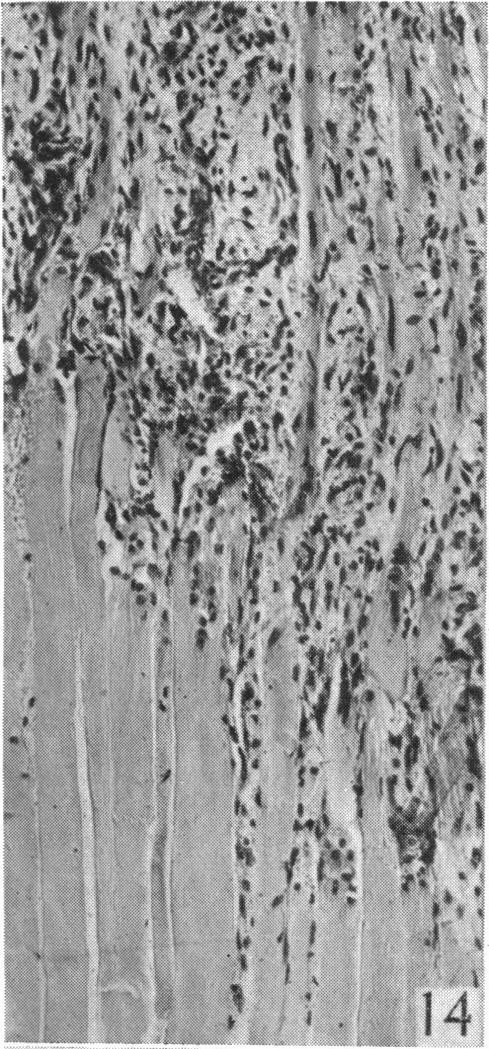

An experimental study of the regeneration of mammalian striped muscle.

摘要